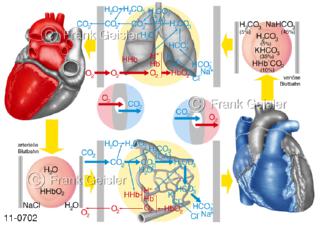

11-0702 Physiologie Atemgastransport, Transport Atemgas in Lunge zum Blut